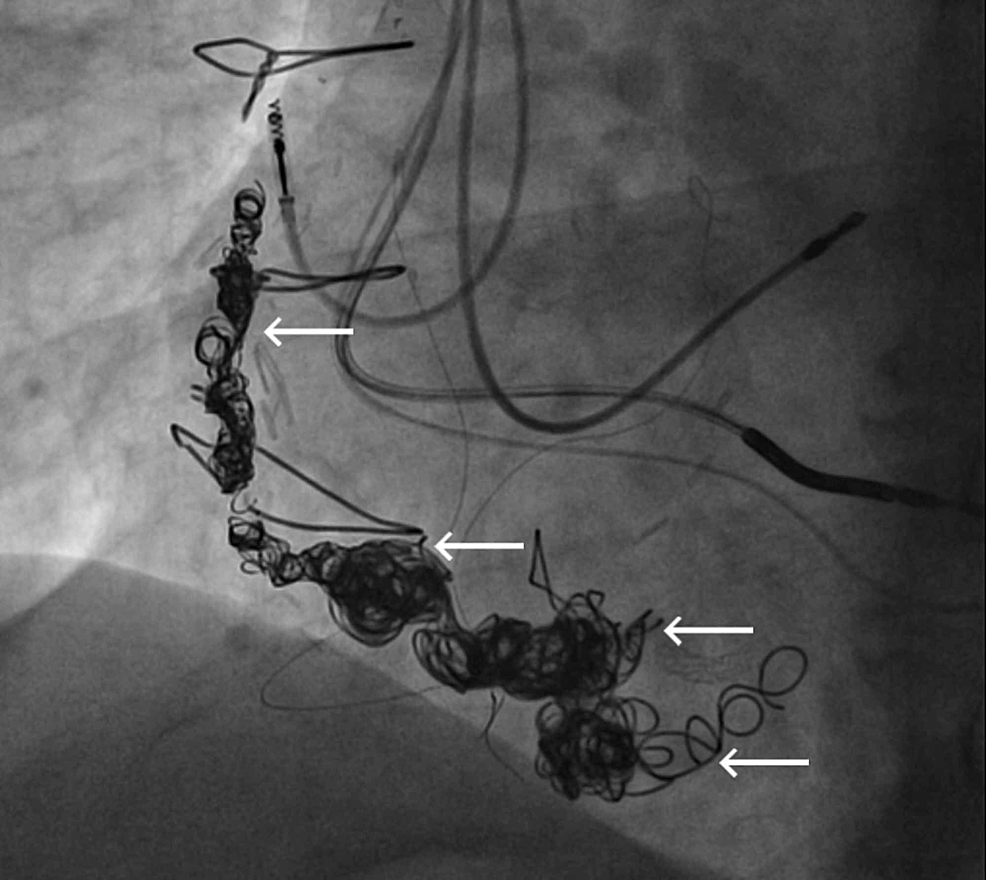

An angiogram revealed something, and he got this form of treatment. ? What is it?

Features of SVG venous graft aneurysm

- Vascular plug

- Multiple coils (Does coil occlusion offer a permanent cure? I can’t think so )

- Covered stent